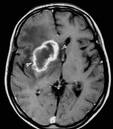

Gliome cérébral

Peut-être vont-elles exiger que des images de gliomes soient désormais présents sur les écrans d'accueil de téléphone portable...